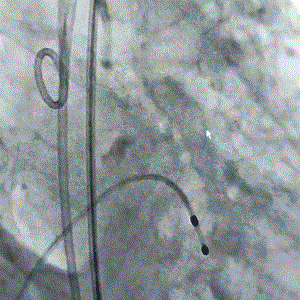

9月27日上午10时,直播开始,魏来教授团队耗时约1小时,经右侧股动脉植入23# Renatus介入主动脉瓣。瓣膜植入位置理想,功能表现出色,造影及经食道超声观察显示瓣膜无中央性返流,轻微瓣周漏,无冠脉血流受阻,无传导阻滞,主动脉瓣峰值流速降至2.0m/s,平均跨瓣压差降至7mm/Hg。手术取得圆满成功。

术前造影(见大量反流)                                   术后造影